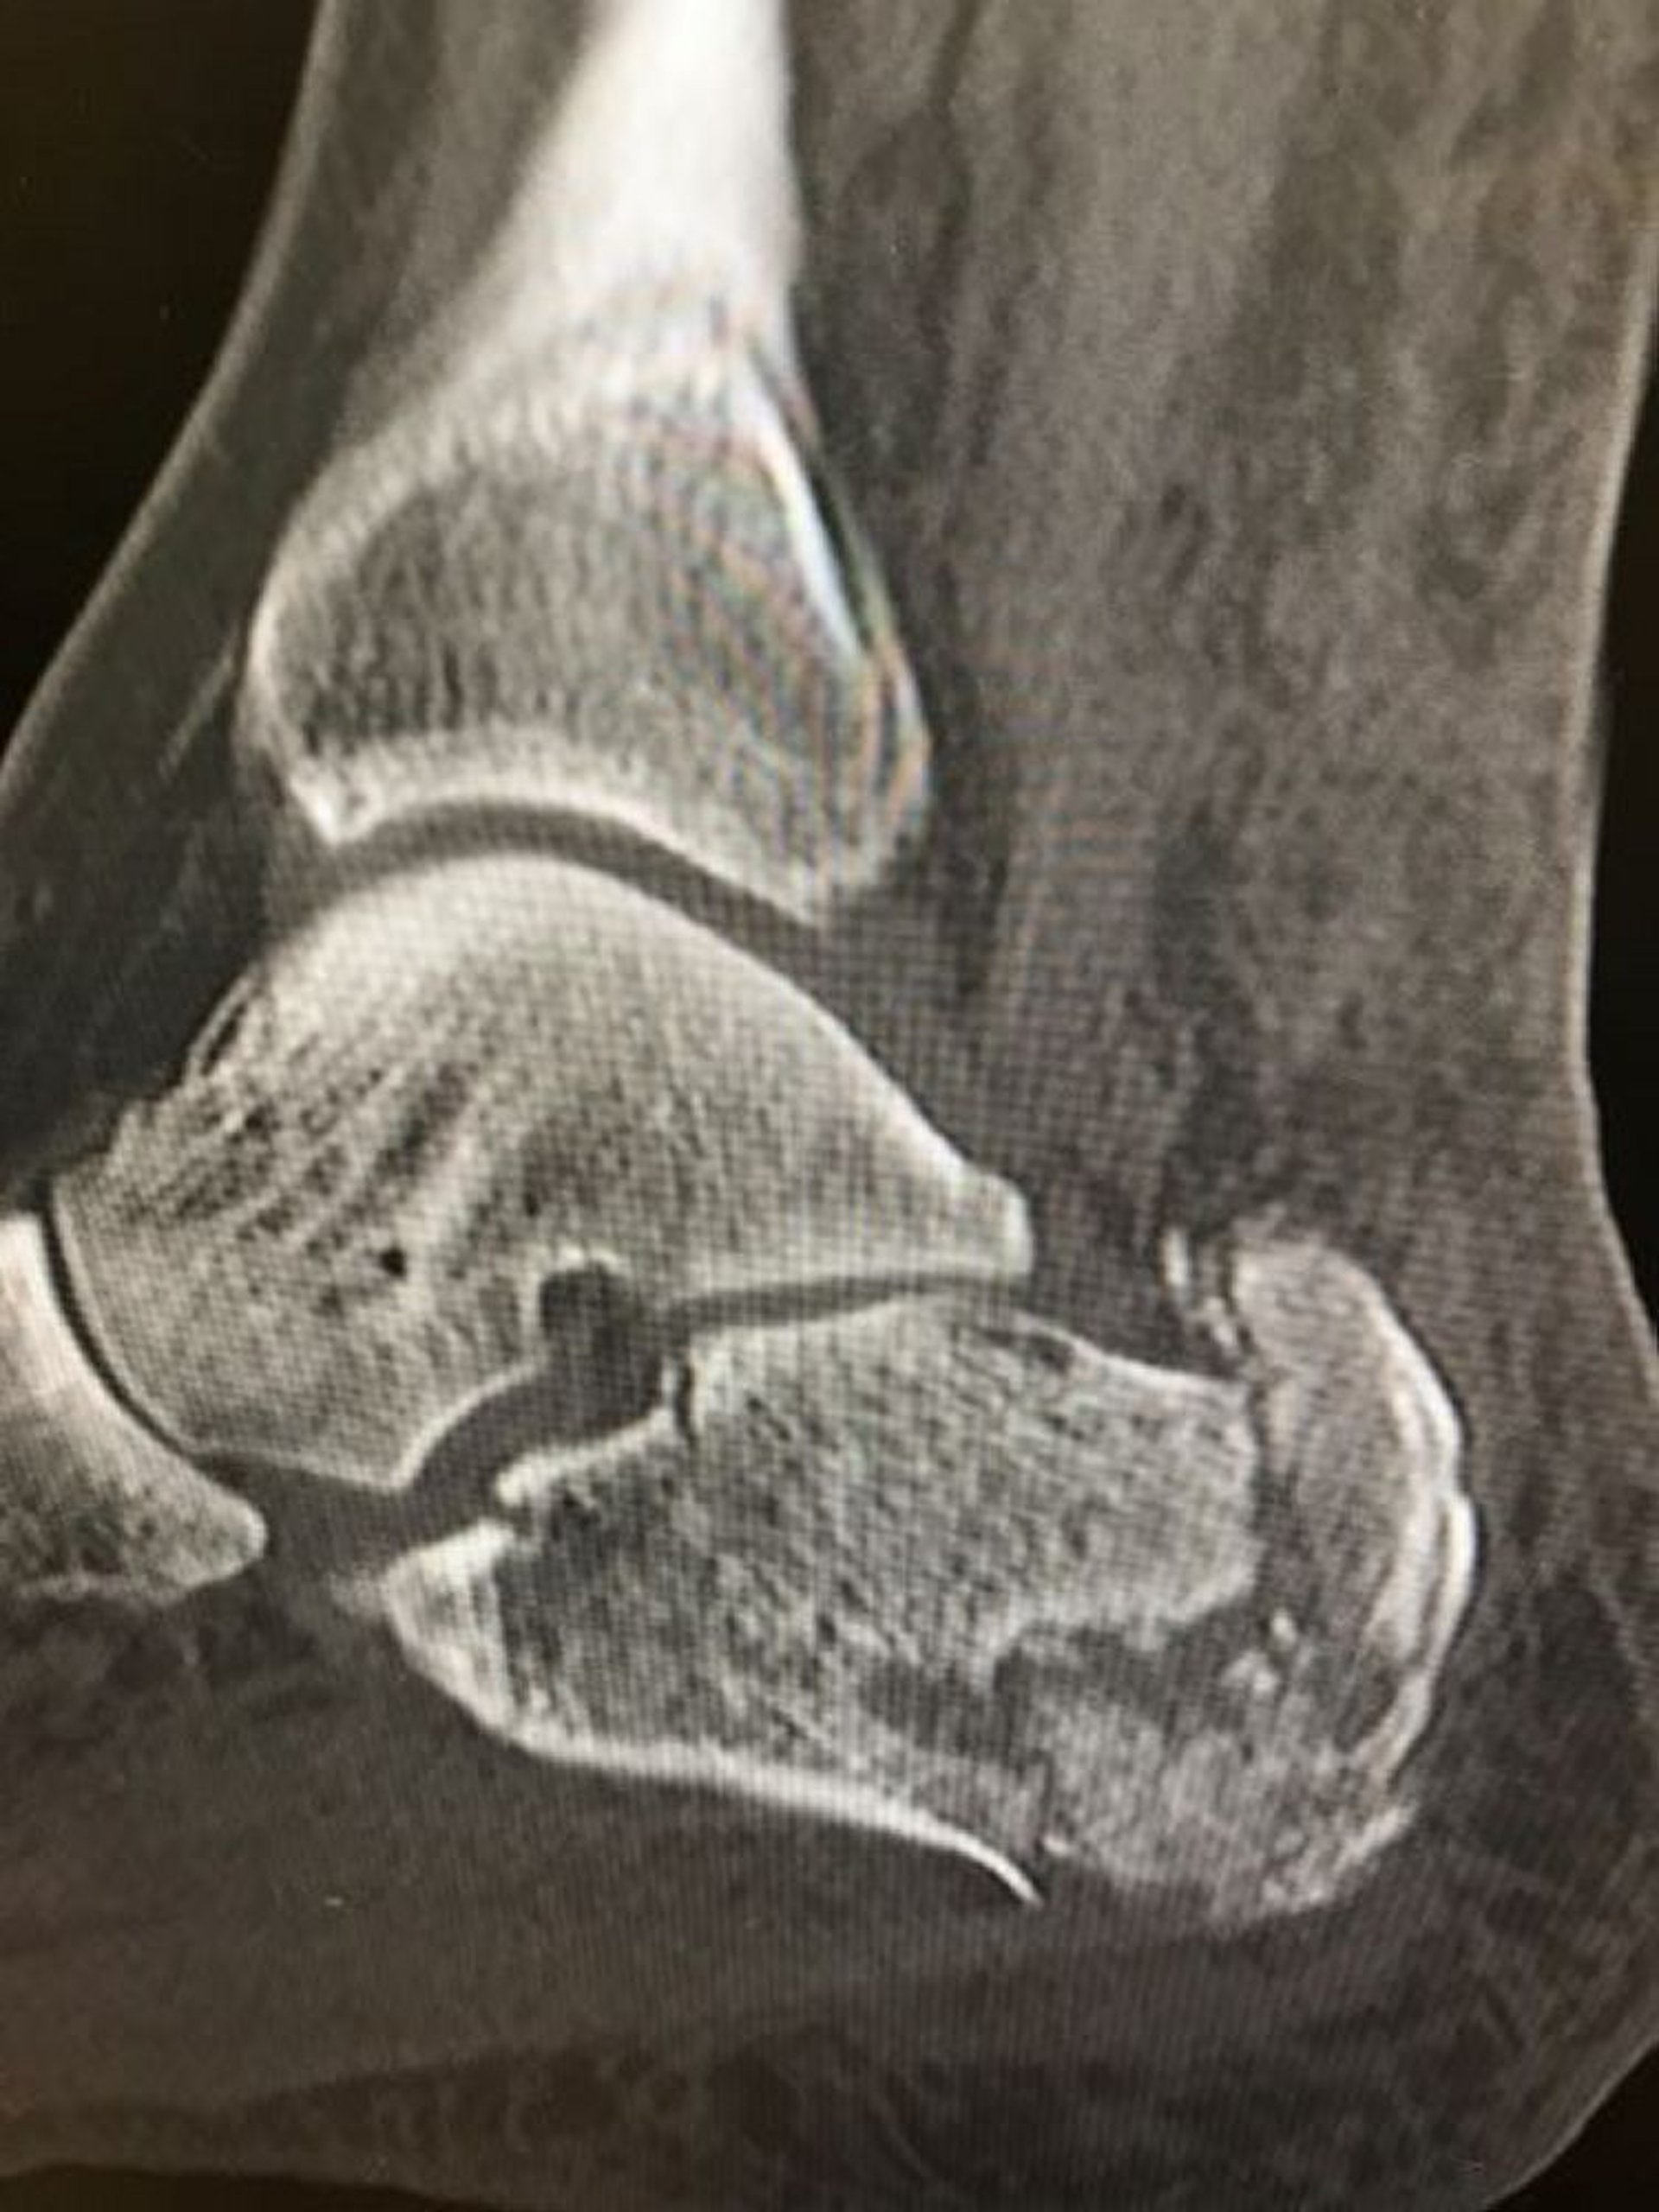

Перелом п'яткової кістки

На даній рентгенограмі показаний уламковий перелом п'яткової кістки.

Знімок люб'язно надано лікарем Даніелем Кампаньє [Danielle Campagne], MD.